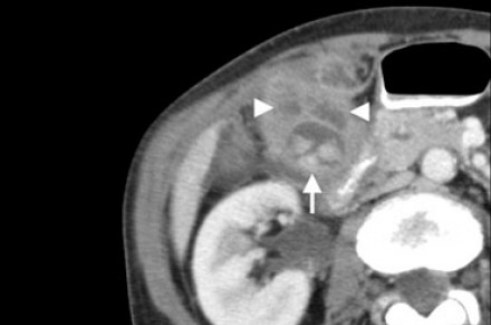

КТ желчного пузыря/Рак желчного пузыря

Наиболее часто встречаемый рак желчного пузыря является карцинома. Карцинома желчного пузыря занимает пятое место по частоте встречаемости среди раков желудочно-кишечного тракта. Чаще его обнаруживают случайно (в 2% случаях) при гистологической проверке после холецистэктомии. Карцинома желчного пузыря выявляется на последних стадиях заболевания так, как себя не проявляет клинически на ранних. Специфических признаков при карциноме желчного пузыря также нет. Рак может поражать желчный пузырь диффузно, целиком стенку или пристеночно. Карцинома желчного пузыря имеет схожую картину с ксантогрануломатозным холециститом, но при постановке диагноза радиологу помогают такие находки:

- Прорастание в соседние органы.

- Вторичная дилатация желчных протоков.

- Метастазирование в печень или лимфатические узлы.

УЗИ (слева) и КТ (справа) желчного пузыря. На УЗИ ярко выраженное утолщение стенки желчного пузыря (указаны белыми стрелками). Множественные камни в просвете желчного пузыря (указано стрелкой). Компьютерная томография с контрастным усилением. На КТ визуализируются утолщение стенки с внутристеночными гиподенсными включениями. На КТ также выявлено, что процесс распространился на печень (указано стрелкой).